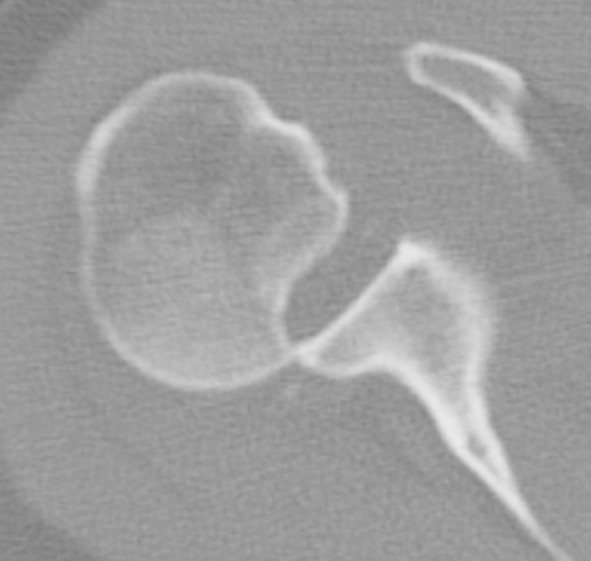

CT scan

Confirms dislocation

Reverse Hill Sachs

Humeral head defect

- caused by impaction of anterior humeral head on posterior glenoid

- intra-articular

- measured as a percentage of the articular surface